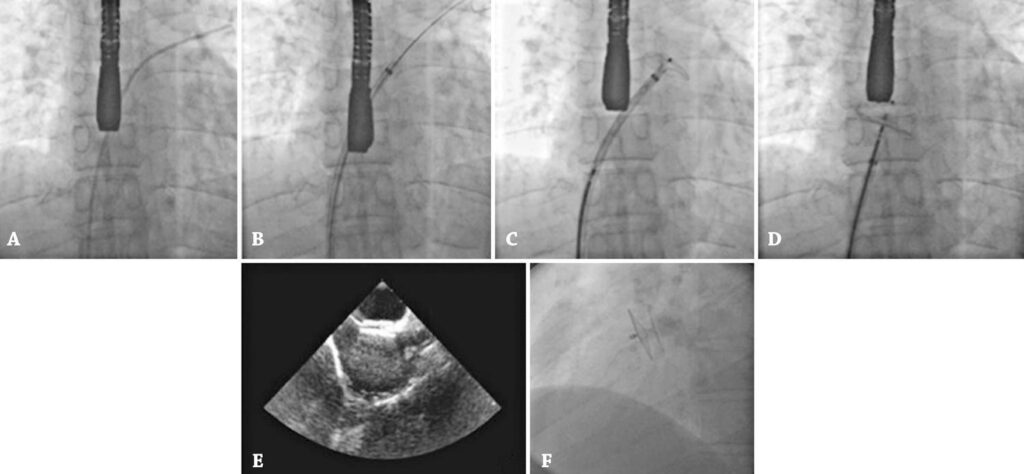

A possibilidade de shunt da direita para esquerda pelo forame oval é causa potencial de embolia paradoxal. A presença de forame oval entre os pacientes com acidente vascular cerebral isquêmico criptogênico em mais de 40% dos casos despertou interesse em avaliar o impacto de seu fechamento na redução de recidiva da doença. O estudo objetiva relatar a experiência de 20 anos com fechamento percutâneo de forame oval realizado por um único operador.

Foram submetidos a fechamento percutâneo de forame oval associado a shunt da direita para esquerda 527 pacientes com acidente vascular cerebral isquêmico.

O procedimento foi realizado com sucesso em todos os pacientes. A média da idade foi de 48 anos (9 a 72 anos), sendo 57% do sexo masculino. Foram implantadas prótese Amplatzer® em 295 pacientes (56%) e Occlutech® em 232 (44%). Não houve mortalidade, e ocorreram as seguintes complicações: hematoma no local da punção em três pacientes (0,6%); fístula arteriovenosa femoral em dois (0,4%) com resolução espontânea; tamponamento cardíaco em dois (0,4%) com resolução após punção e drenagem; arritmia supraventricular transitória em três (0,6%); cefaleia em 27 (5,1%); fibrilação atrial em dois (0,4%); shunt residual grande com necessidade de segunda prótese em dois pacientes (0,4%); recorrência de acidente vascular cerebral isquêmico em seguimento em 5 anos em quatro (0,8%) e hipersensibilidade ao níquel em uma paciente (0,2%).

A oclusão de forame oval como prevenção de recorrência de acidente vascular cerebral isquêmico nessa série se mostrou segura, eficaz e com baixo índice de recidiva em 5 anos de seguimento.